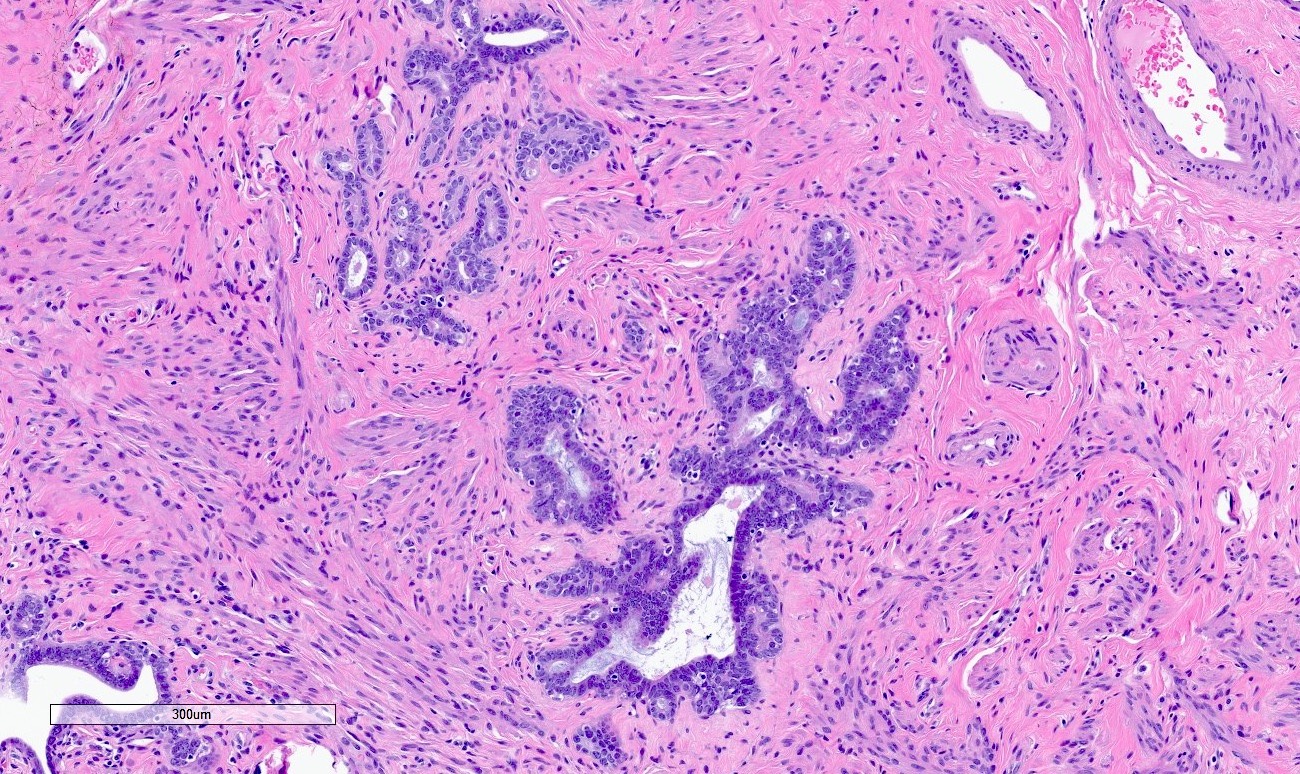

Microscopic (histologic) description

- Regularly spaced glands lined by normal appearing tubal epithelium surrounded by smooth muscle or fibrous tissue

- Tubal lumina are true diverticula that communicate with the central tubal lumen but do not connect with the serosa

- Glands can become cystically dilated (Am J Clin Pathol 1951;21:212)

- No significant atypia, scarring or associated inflammatory / stromal response

- Absence of endometrial stroma differentiates this entity from tubal endometriosis

Microscopic (histologic) images